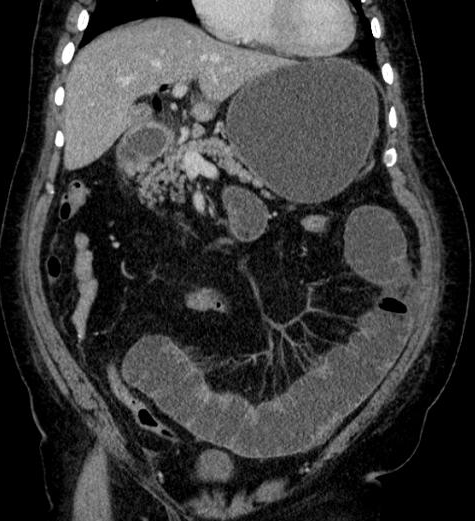

Meme cas en coupe coronal ( frontal ) :

Image de calcul hyperdense se en voyait tres net (

fleche rouge ) avec image de vesicule biliaire

inflamee et la dilatation de canal hepatique commun |